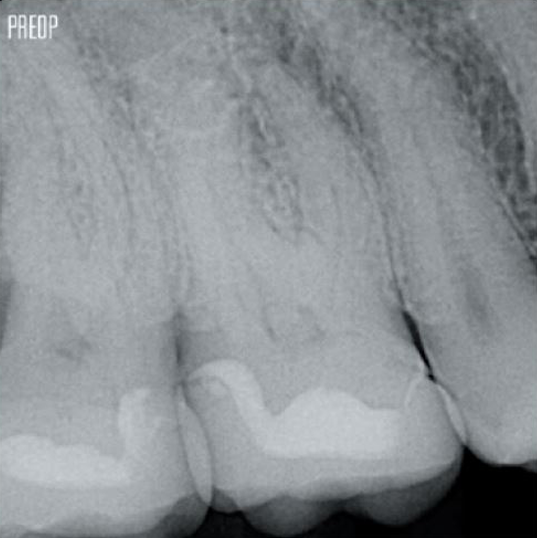

Fotos cortesía del Dr. Ahmed Salman

Más dentina conservada. Conformación, irrigación y obturación adecuadas.

El tratamiento satisfactorio del conducto radicular comienza con un acceso adecuado a la cámara pulpar. El procedimiento ideal proporciona acceso a los orificios de los conductos radiculares con una pérdida mínima de dentina.

Se recomienda una cavidad de endodoncia conservadora (CEC) con el sistema TruNatomy®.

El acceso ahora es posible desde diferentes ángulos, mientras que, hasta ahora, la estructura debía sacrificarse (cavidad de endodoncia tradicional).1

Sin necesidad de acceso en línea recta.1

La unión de la geometría de la lima, las conicidades regresivas y el alambre delgado y altamente flexible permite un tratamiento eficiente del conducto radicular al tiempo que se elimina solo la dentina cuando es clínicamente necesario.1